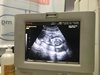

Płeć w 18 tygodniu.

Cześć :) czy płeć można już określić w 18tc?

Czy te dwie kulki miedzy nogami mogą wskazywac na chłopca? Dolaczam zdj.